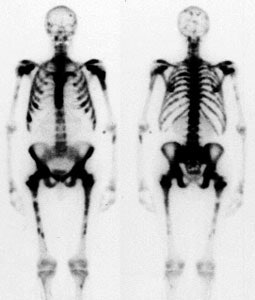

"Superscan" in patient with prostate cancer: A "Superscan" occurs in a patient with widespread osteoblastic bone metastatses. There is diffuse, intense skeletal uptake of the tracer with absent renal and background activity. |